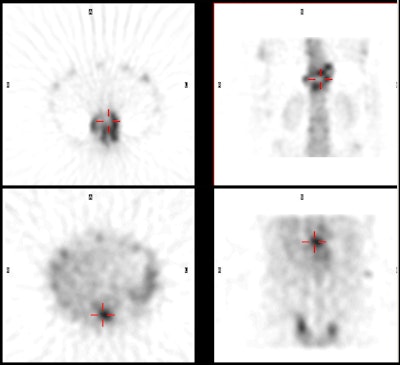

Spinal osteomyelitis: The patient

below was being evaluated for possible spinal

osteomyelitis. The SPECT bone scan (top images)

demonstrated an area of abnormal tracer uptake in the

lower thoracic spine with a cenrtal area of photopenia

(crosshairs). The SPECT gallium images (below)

demonstrated focal gallium concentration in the region of

photopenia- a pattern that was incongruent to the bone

scan and consistent with osteomyelitis. |